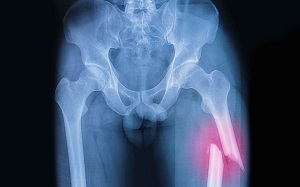

Перелом диафиза бедренной кости

Разным может быть уровень костной деформации:

- Верхняя треть;

- Средняя часть;

- Нижняя треть.

Виды переломов с учетом характера плоскости повреждения:

- Косой;

- Поперечный;

- Оскольчатый;

- Винтовой;

- Двойной.

После получения травмы проверяется пульс артерий, чувствительность стоп. Для постановки точного диагноза делается рентген.